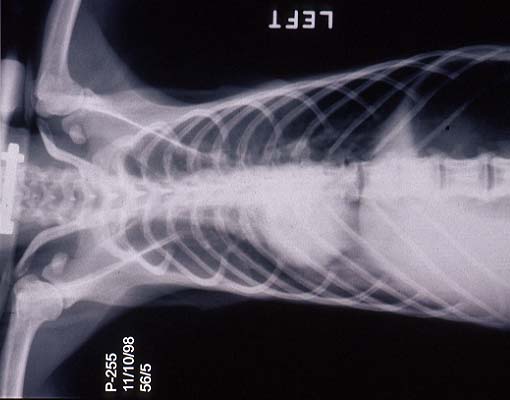

- Case 23-1. Chest radiograph. Diffusely lung fields

are infltrated by flocculent fluid densities.